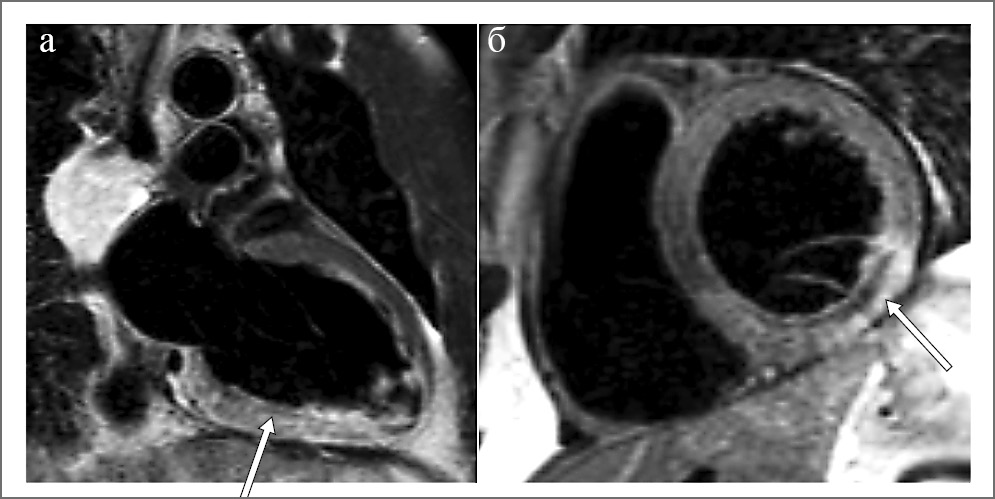

Кино-МРТ – это импульсная последовательность, позволяющая получить изображения сердца в стандартных проекциях (2- и 4-камерная длинные оси, короткая ось ЛЖ) в виде кинопетли. Этот режим является эталоном оценки объемов, глобальной и региональной сократимости ЛЖ и ПЖ (рис. 2).

Рис. 2. Кино-МРТ: а – 2-камерная длинная ось ЛЖ; б – 2-камерная короткая ось ЛЖ

Благодаря четкой визуализации границ эндокарда, высокой воспроизводимости и операторонезависимости метод кино-МРТ позволяет точно выявить и оценить зоны нарушения локальной сократимости, в том числе при повторных исследованиях.

МРТ позволяет точно оценить процессы патологического ремоделирования на фоне различных сердечно-сосудистых патологий и обратного ремоделирования вследствие проводимой терапии. Эти показатели играют важную роль в оценке прогноза больных с острым ИМ и контроле эффективности лечения [16].